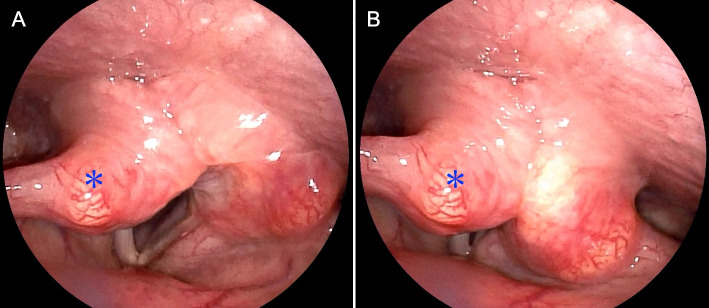

Case presentation: A 59-year-old Japanese female presented with hoarseness and pharyngeal discomfort. Endoscopic examination revealed fixation of the right vocal cord, presumably due to right RLN palsy. Ultrasonography and computed tomography showed an ill-defined thyroid mass lesion in the right lobe, strongly suggestive of malignancy, although repeated aspiration cytology revealed no suspicion of malignancy. Intraoperatively, because the right RLN was found to be entirely embedded within the hard mass lesion and completely unresponsive to nerve integrity monitoring, the nerve was unavoidably excised along with the right lobe. Histopathology led to the final diagnosis of nodular goiter, wherein the resected RLN was severely degenerated and disrupted due to intense chronic inflammation accompanied by perineural fibrosis.